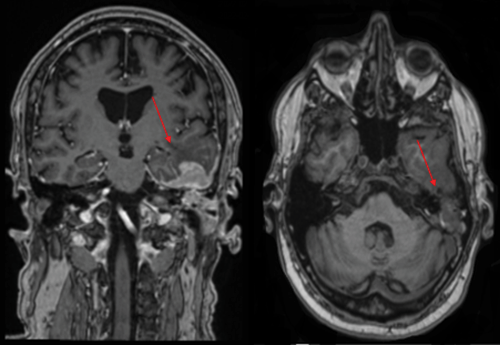

A magnetic resonance imaging (MRI) study of the brain was performed. The imaging results revealed intracranial lymphomatous masses localized within the left side of the temporal basal region (Figure 3).

Figure 3. MRI scans of the brain (coronal and axial view). Arrows showing intracranial lymphomatous masses in the left temporal basal region, involving the left petrous pyramid and mastoid process